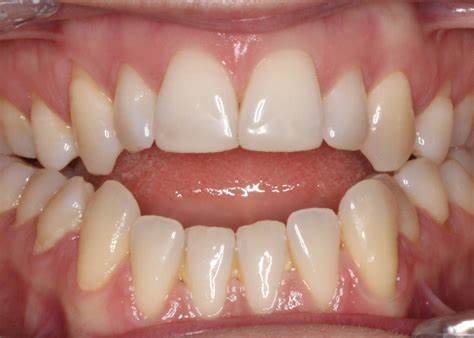

Malocclusion

Clinical Presentation: Misaligned teeth, difficulty chewing, jaw pain, and TMJ discomfort.

Zebris Findings: Abnormal or uneven jaw movements, discrepancies in occlusal contacts, and uneven load distribution across the TMJ.